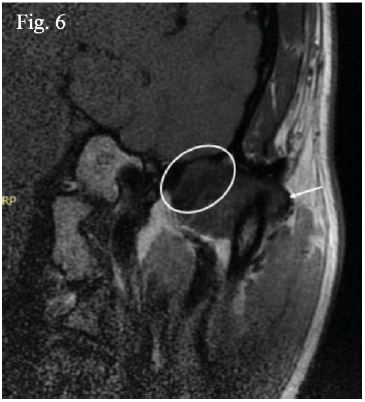

Además, debe tenerse en consideración que hasta hoy la mayoría de los resonadores utilizados son de 1.5 tesla mientras que aquellos de mayor potencia de campo magnético brindan imágenes con mayor precisión diagnóstica41. Por eso, creemos que varios artículos no han logrado diferenciar estas estructuras por los factores inherentes del equipo resonador. Para graficar esto, en la imagen (figura 5) presentada por Orhan et al., en el año 2005 se puede ver claramente lo imposible que resulta diferenciar el disco de la cápsula articular42. A medida que la tecnología va evolucionando, autores como Wang, Yang y Yu en el año 2009 ya mencionan su visualización en T1 y con una densidad muy similar a la del disco articular particularmente cuando se observa en la reformación coronaria17. Luego ya para el año 2015 Hagenkord y Basel presentaron imágenes de la cápsula articular donde la definieron con una densidad similar a la de la cápsula, como fue comentado anteriormente ya que están conformadas por el mismo tejido43; así, con una imagen de archivo queremos demostrar que la imagen del disco articular puede ser diferenciada de la cápsula articular (figura 6).